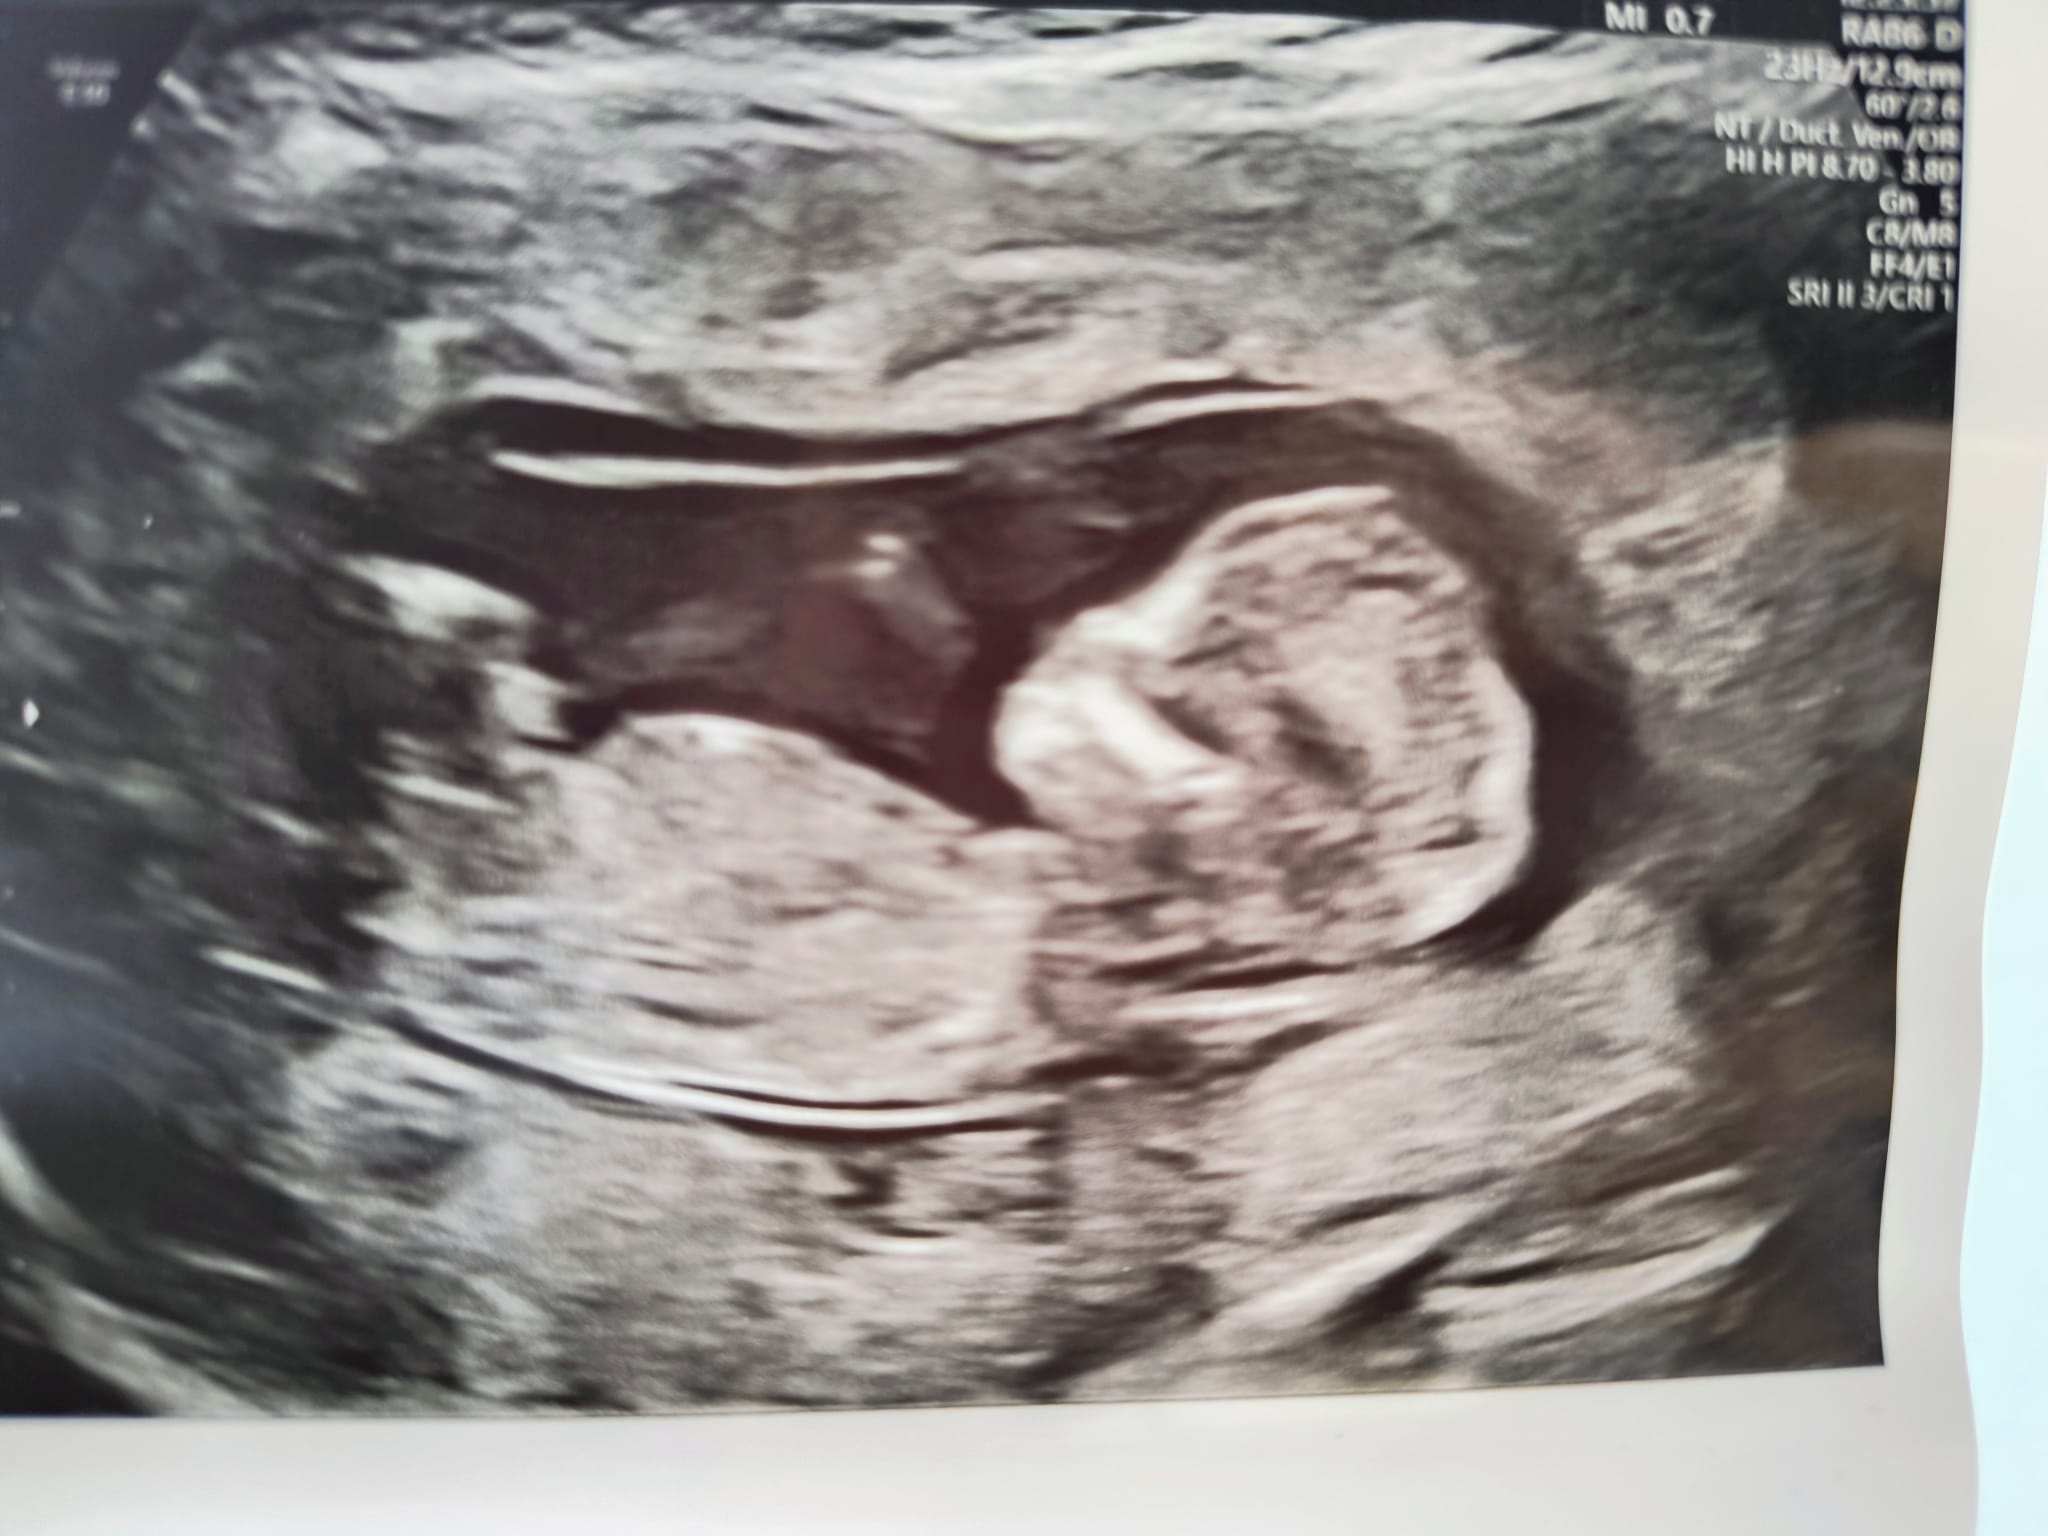

Cześć forumowe Cioteczki,

dziś u nas przełom i wreszcie pierwszy raz wzięliśmy głębszy oddech.

Za nami badania prenatalne i dobre wieści - nie ma powodów do niepokoju, ryzyka niskie, wszystko gra.

Dzidzior jest kilka dni do przodu. Wg transferu termin porodu na 5 września, wg CRL - 31 sierpnia.

Kolejna wizyta za miesiąc, wtedy powinniśmy poznać płeć.

Zaczynam wierzyć, że to się dzieje naprawdę 🥹